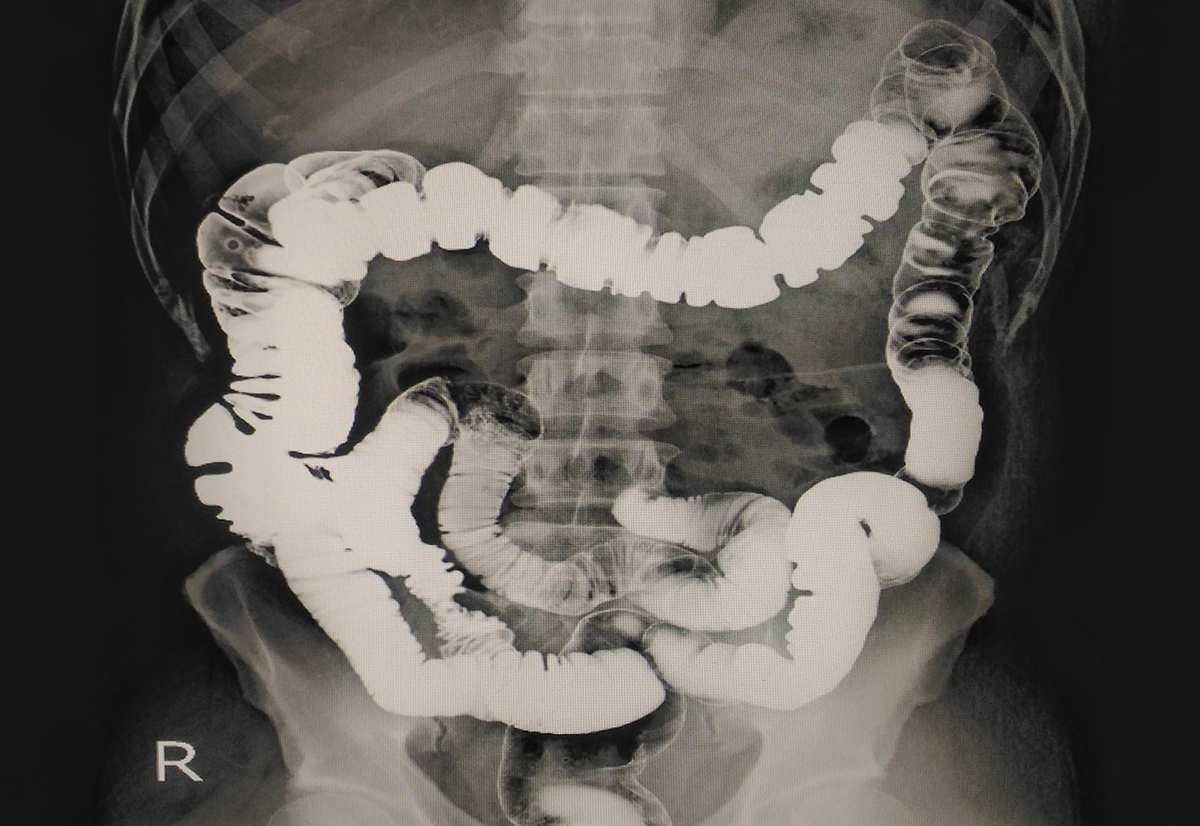

ナイアシンが欠乏すると、「4D症状」として知られる皮膚炎(Dermatitis)、下痢(Diarrhea)、認知障害(Dementia)、死(Death)が特徴的なペラグラ(pellagra)を引き起こします。

なかでも慢性的な下痢や消化不良は、ペラグラの初期症状としてしばしば現れます。[2]

これは、ナイアシン不足によって腸粘膜の細胞再生やエネルギー産生が阻害され、バリア機能が低下するためと考えられています。